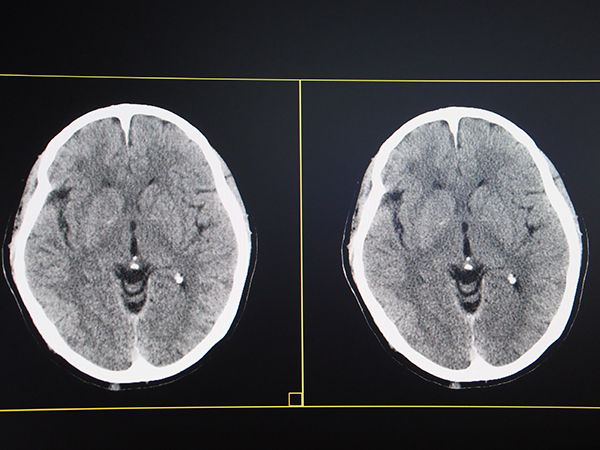

逐次近似画像処理“IPV”は,自然な質感を保ったまま,最大90%の画像ノイズ低減や,最大83%の被ばく低減などを可能にし,低被ばくと高画質を高いレベルで両立できる画像処理法である。今回,適応領域が従来の腹部だけでなく,頭部や胸部も含めた全身へと広がった。高画質化についてはさらに,金属アーチファクト低減技術“HiMAR”が進化し,“HiMAR Plus”が追加された。HiMAR Plusは,rawデータとイメージデータの両方で繰り返し再構成を行うことで,より強いアーチファクトを抑制することができる。画像処理の強度は,standardとstrongの2段階が用意されている。アーチファクトを除去しやすい腰椎などには高速に処理できる従来のHiMARを,大腿や膝など大きな金属が入っている部分にはHiMAR Plusを使用するなど,撮影画像を確認して必要に応じた処理が可能になる。

金属アーチファクト低減技術は“HiMAR Plus”に進化(左上:通常画像,右上:従来のHiMAR,左下:HiMAR Plus standard,右下:HiMAR Plus strong)